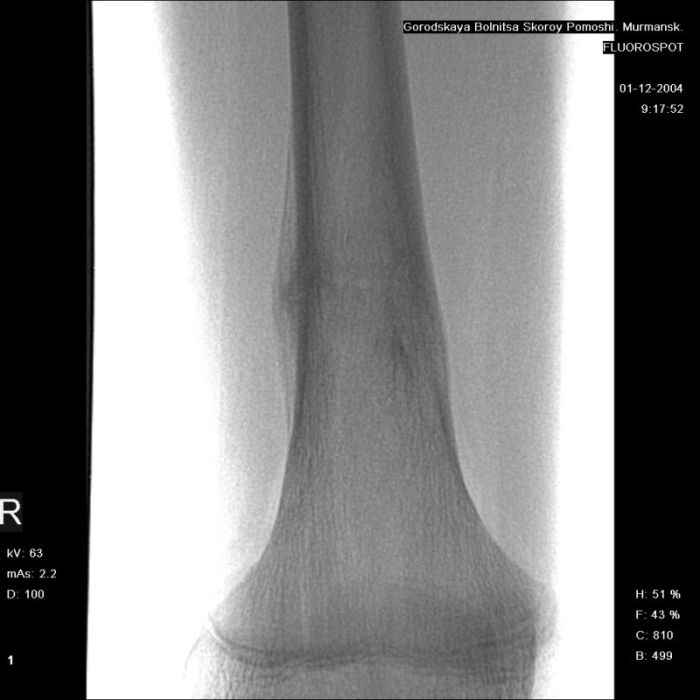

Здравствуйте, уважаемые коллеги!Представляю вашему вниманию интересный случай и пока что непонятный для меня в диагностическом плане. На днях в наше отделение (детской ортопедии и травматологии) поступил 13-летний мальчик по направлению из поликлиники с диагнозом: остеома нижней трети правого бедра.

Анамнез практически никакой: в следствие травмы (растяжение связок коленного сустава) от 07.11.2004 выполнены Rg-граммы в травмпункте и обнаружено опухолевидное образование. Первичные Rg-граммы я не публикую, так как они заметно худшего качества, да и динамики за прошедшие три недели не отражают. Болевой синдром купирован в течение трёх дней. В настоящий момент мальчика ничего не беспокоит. Ходьба не нарушена, опухоль пальпируется с трудом по задней поверхности в н\3 правого бедра, пальпация безболезненна, объем движений в суставах правой нижней конечности полный и симметричный. Кожа над опухолью не изменена.В нашей клинике проведено дополнительное обследование: общие анализы крови и мочи, биохимия крови без особенностей. Выполнены Rg-граммы на цифровом Siemens обычные и продольные томограммы срезами 3-5 мм, а также компьютерная томография поперечными срезами по 5 мм. Прошу обратить внимание, что на приведённых томограммах видны две полости 10х15 мм и 15х60 мм. Также имеются два опухолевидных образований наслаивающихся друг на друга: уплощённое и вытянутое 10х100 мм и элипсовидной формы 15х30 мм. Это хорошо заметно на фото a_1.jpg c_1.jpg и d_1.jpg. Плотность внутри полостей 125% от плотности костномозгового канала, плотность наружного опухолевидного образования 55% от плотности кортикального слоя. Также отмечается линия перелома по центру наружного опухолевидного образования.Исходя из полученных данных мнения в плане диагноза несколько разделились от 1)сочетания кортикальной фиброзной дисплазии и латентно протекавшего маршевого перелома н\3 правого бедра до 2)остеосаркомы. В отношении первого варианта не сходится отсутствие клиники при переломе такой крупной кости как бедро, второй вариант вообще оставлю без комментария, ибо некомпетентен. Хотелось бы услышать мнения коллег, с удовольствием ознакомлюсь с любыми предположениями и замечаниями.С уважением, Александр Е. КлоковОтделение детской ортопедии и травматологииБСМП г. Мурманска.